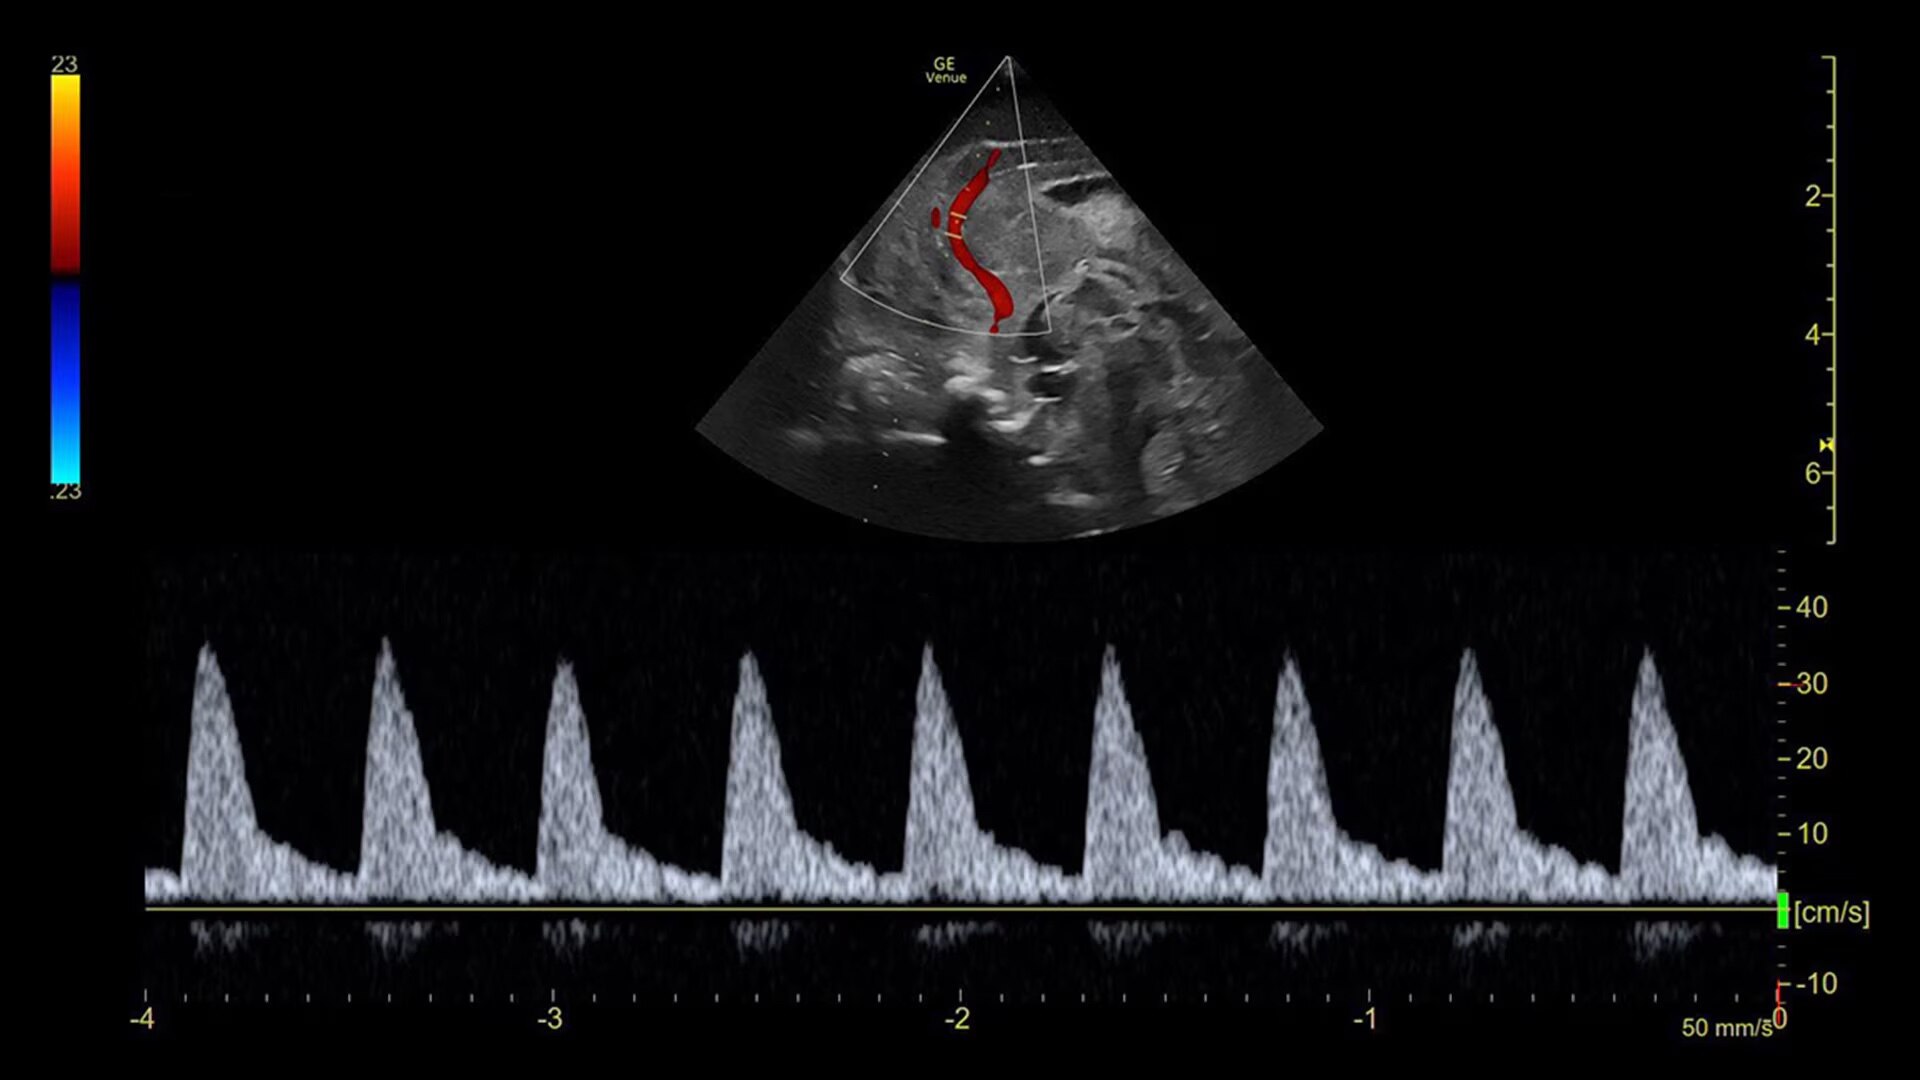

Access accurate, instant, and rapidly updating results with Real-Time EF

Capture precise results instantly without requiring ECGs through Real-Time EF*, an AI tool that continuously calculates real-time ejection fraction during live scanning in apical 4CH view.